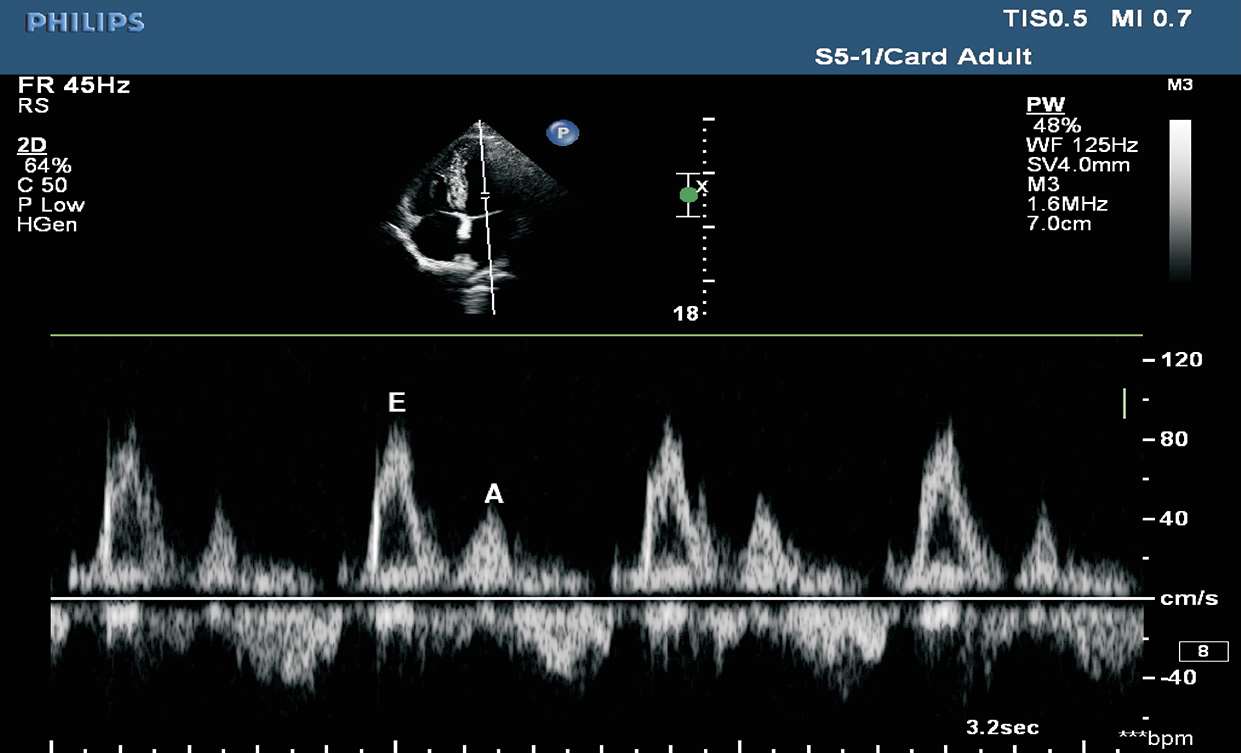

二尖瓣脉冲型频谱多普勒取样框置于二尖瓣瓣尖水平,取样线平行于血流。二尖瓣舒张期血流频谱包括舒张早期血流快速充盈产生的E峰及舒张末期心房收缩产生的A峰(见图1-34)。

图1-34 二尖瓣脉冲型频谱多普勒

(1)二尖瓣口血流脉冲多普勒频谱。取样框置于二尖瓣瓣尖水平,取样线平行于血流。二尖瓣舒张期血流频谱包括舒张早期血流快速充盈产生的E峰及舒张末期心房收缩产生的A峰。正常状态下:E峰/A峰>1;E峰最大流速:平均73 cm/s;A峰最大流速:平均40 cm/s;E峰减速时间(EDT):166±4 ms(见图1-40)。

图1-40 二尖瓣口血流脉冲多普勒频谱